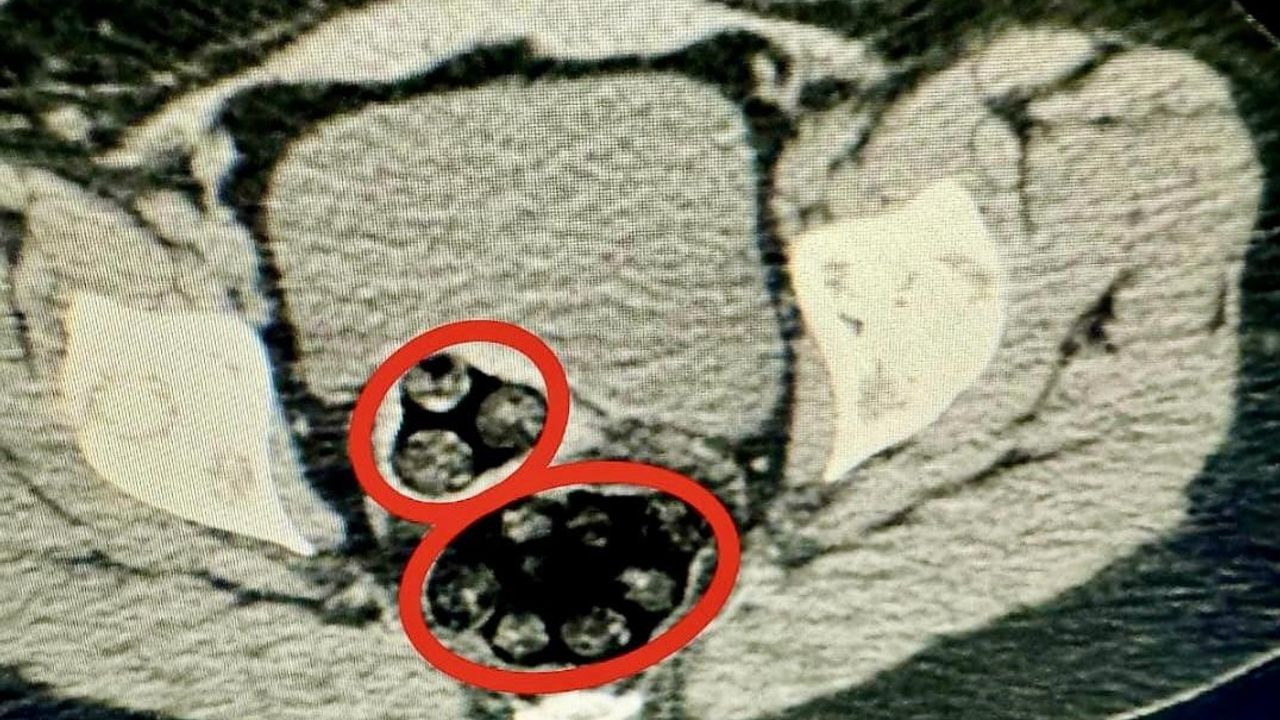

94 parça uyuşturucu cerrahi müdahale ile çıkarıldı

Otobüste gözaltına Fahımeh Golmohammadı Yenkejeh’in yapılan iç beden muayenesinde makadında cisim olduğu tespit edildi. Fahımeh Golmohammadı Yenkejeh’in makadına saklanmış bir şekilde 94 parça 550,63 gram metamfetamin uyuşturucu maddesi cerrahi müdahaleyle çıkarıldı.